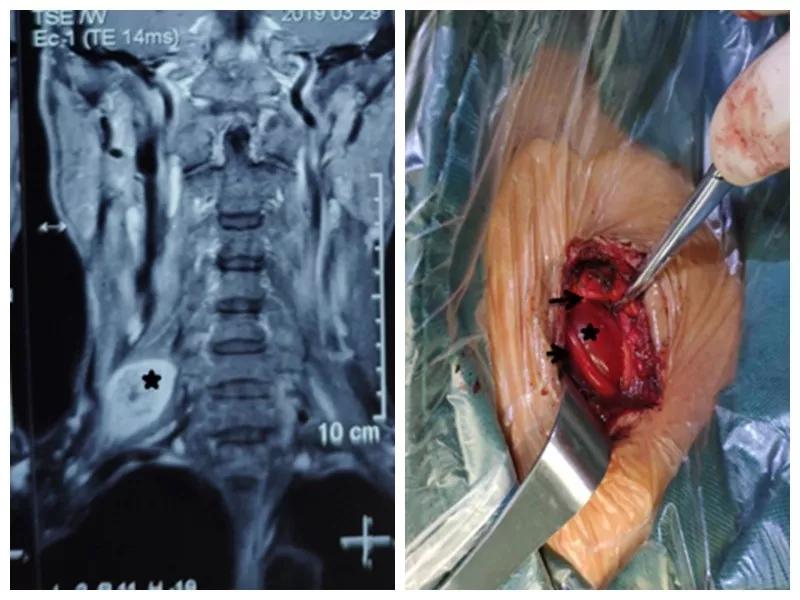

家住户县的王师傅一年前无意中发现右颈部长了一个“包”,当时并未在意,但是他发现这个“包”逐渐增大,并且伴有压痛,按压这个“包”时还可引起右胳膊疼痛,在当地21点游戏规则 就诊,未见好转,在我市某三甲21点游戏规则 检查及包块穿刺活检示右侧颈部神经鞘瘤,医生告诉他可以手术切除,但是风险很大。王师傅慕名来到21点玩法研究所 骨一科就诊,严少荣主任接诊后立即安排住院治疗,并安排由西安市手外科常委王涛主任医师及主治医师张磊组成治疗小组。积极进行术前检查,发现右颈部肿瘤有3×3×3 cm大小活动性差的肿瘤。并有触电样感觉向肢体放射。经过制定缜密手术方案,严主任细心耐心告知患者手术的风险性,并安排术中神经电生理监测,提高手术安全性,由王涛主任医师、张磊主治医师和麻醉医师李楠及手术护士组成手术团队,在全麻下行右侧颈部神经鞘瘤切除术,术中发现此神经鞘膜瘤巨大,位于臂丛神经上干并包饶颈5.6神经,与周围组织黏连严重,由于该肿瘤起源于神经根纤维许旺氏细胞,遂着肿瘤不断生长,将神经干内正常神经纤维挤向肿瘤四周,包含在神经外膜内形成肿瘤的“包膜”呈鱼肉样。王涛主任医师在仔细保护神经的情况下采用“层层剥离挤出法”将肿瘤取除,避免了误将含正常神经纤维的“包膜”随肿瘤一起切除,造成神经干损伤及缺失,从而造成上肢功能的不可逆障碍的悲剧。术后经过主管护士解妍及全体医护人员的精心治疗护理,王师傅原有神经压迫症状消失,无任何感觉运动异常,术后再次病检符合神经鞘瘤。王师傅满意出院。

通过此例罕见臂丛神经上干神经鞘瘤病人治疗,标志着我科在高位臂丛神经干手术达到一个新高度。